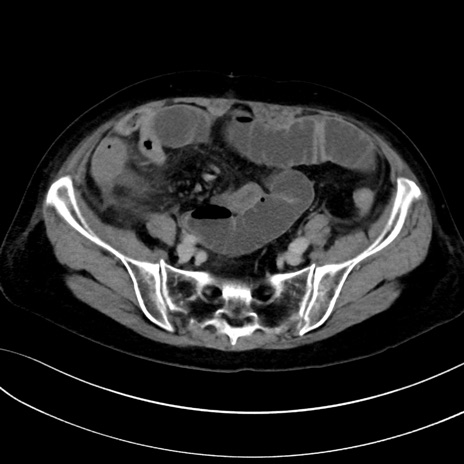

症例13 CT(横断像)1日半後